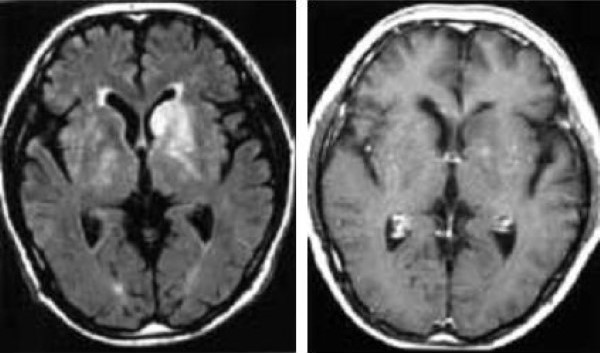

Đột quỵ thiếu máu cục bộ cấp có thể biểu hiện là một tổn thương não có giới hạn không rõ ràng, gây hiệu ứng khối, nhu mô tổn thương ngấm thuốc tương phản hoặc không [8]. Các dấu hiệu hình ảnh này tương tự với dấu hiệu của u thần kinh đệm (glioma). Trong các tình huống này, chụp cộng hưởng từ khuếch tán (diffusion-weighted imaging) có thể khá hữu ích, cho dù không nhất thiết để kết luận. Nếu không có cộng hưởng từ khuếch tán, việc phân biệt giữa đột quỵ thiếu máu cục bộ cấp và u não là khó ở các bệnh nhân không có tiền sử lâm sàng rõ ràng (Hình 1a và 1b). Theo dõi bằng hình ảnh trong một thời gian ngắn là cần thiết để chẩn đoán nhồi máu não trong các trường hợp này (Hình 1c và 1d) [8].

Hình 1 a/b. Glioma? Bệnh nhân nam 65 tuổi biểu hiện rối loạn dáng đi từ từ. (Chẩn đoán cuối cùng: nhồi máu não theo sự phân bố của động mạch vân trong).

a và b: MRI lúc nhập viện

a: một vùng tăng cường độ ở đầu nhân đuôi trái kéo dài tới phần trước của nhân vỏ sẫm trái trên ảnh FLAIR (TR/TI/TE 9000/2350/ 119) với một hiệu ứng khối ép sừng trán trái não thất bên. Vùng cường độ cao này phù hợp với sự phân bố của động mạch vân trong.

b: ảnh spin-echo (SE) T1-W (TR/TE 600/50) sau tiêm thuốc đối quang từ thấy tổn thương không ngấm thuốc. MR angiography (MRA)(không trình bày) bộc lộ tắc đoạn gần động mạch quặt ngược Heubner trái.

Hình 1 c/d: Chụp MRI 6 tuần sau

c: ảnh FLAIR (9000/2350/119) cho thấy sự co lại của vùng tăng cường độ ở phần trước của nhân nền trái. Sự chèn ép sừng trán trái đã biến mất.

d: ảnh SE T1-W (600/15) cho thấy tăng cường độ ở đầu nhân đuôi trái biểu hiện chảy máu.